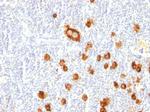

CD15/FUT4 (Reed-Sternberg Cell Marker) Recombinant Rabbit Monoclonal Antibody (FUT4/1478R)

NeoBiotechnologies

应用

IHC (P) IHC (PFA) ICC/IF Flow